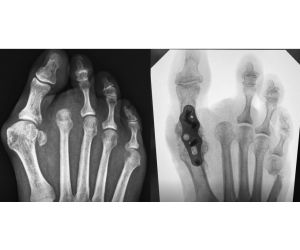

Transfer Metatarsalgia after MIS Hallux Valgus

Patrick DeHeer, DPM

One of the biggest knocks on MIS bunion surgery is transfer metatarsalgia. The assumption has always been that the burr causes shortening and that...